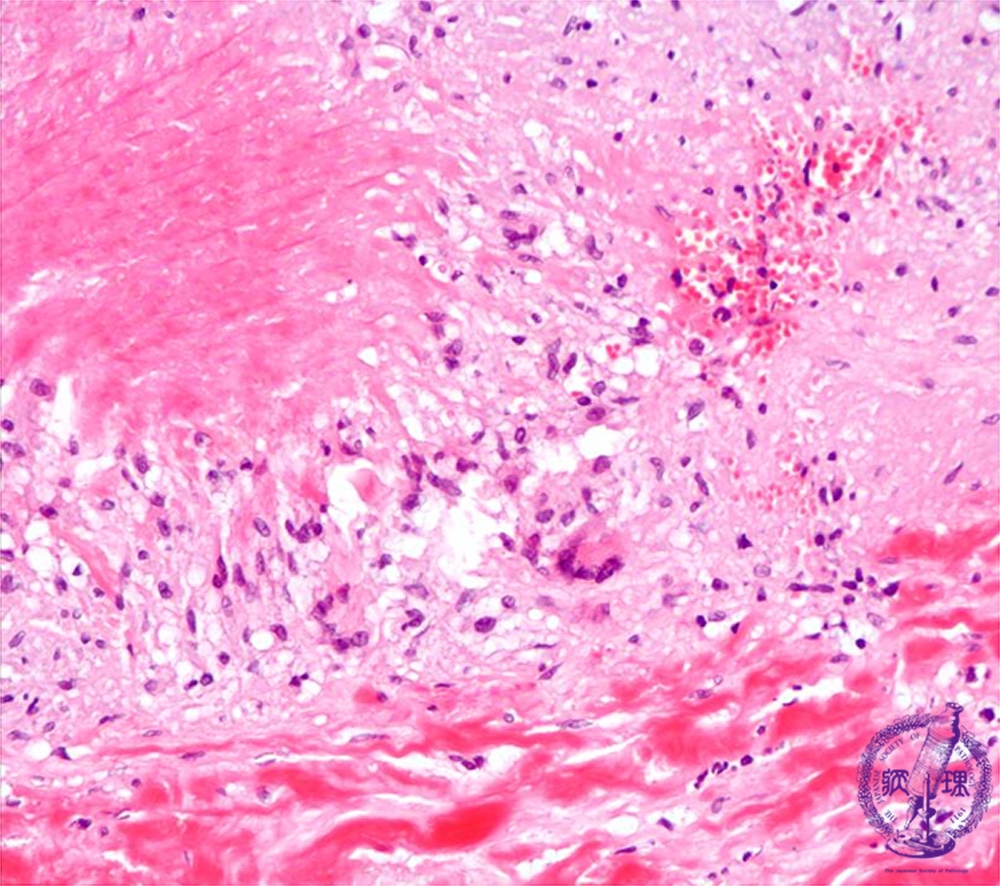

- (13)Takayasu arteritis

Microscopic image (HE, high power view): There is necrotizing, granulomatous inflammation composed of a Langhans giant cell infiltrate and central necrosis at the rupture site of the elastic lamellae.